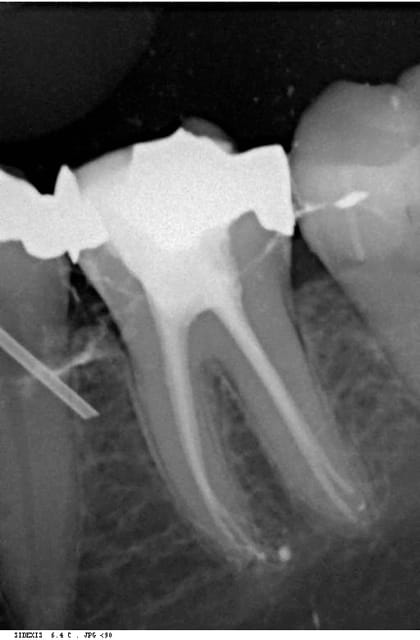

voilà une endo réalisée sans radio préop avec un localisateur chinois à 170 usd.

le truc c'est que je n'arrive pas à le brancher sur secteur, prises inadaptées, et il faut que la pile soit au max pour une précision acceptable.